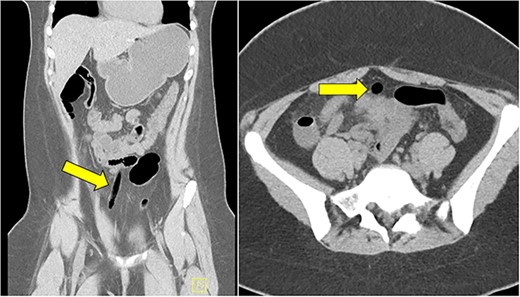

Computed tomography (CT) abdomen and pelvis demonstrated an air-filled tract from the pelvis to mid abdomen, suggestive of a foreign body in the anterior abdomen at the level of the umbilicus (Fig. 1). The radiology report for this CT scan suggested that this foreign body may be located within the urachal remnant.

CT scan of abdomen and pelvis showing the presence of an air-filled foreign body in coronal and axial view.